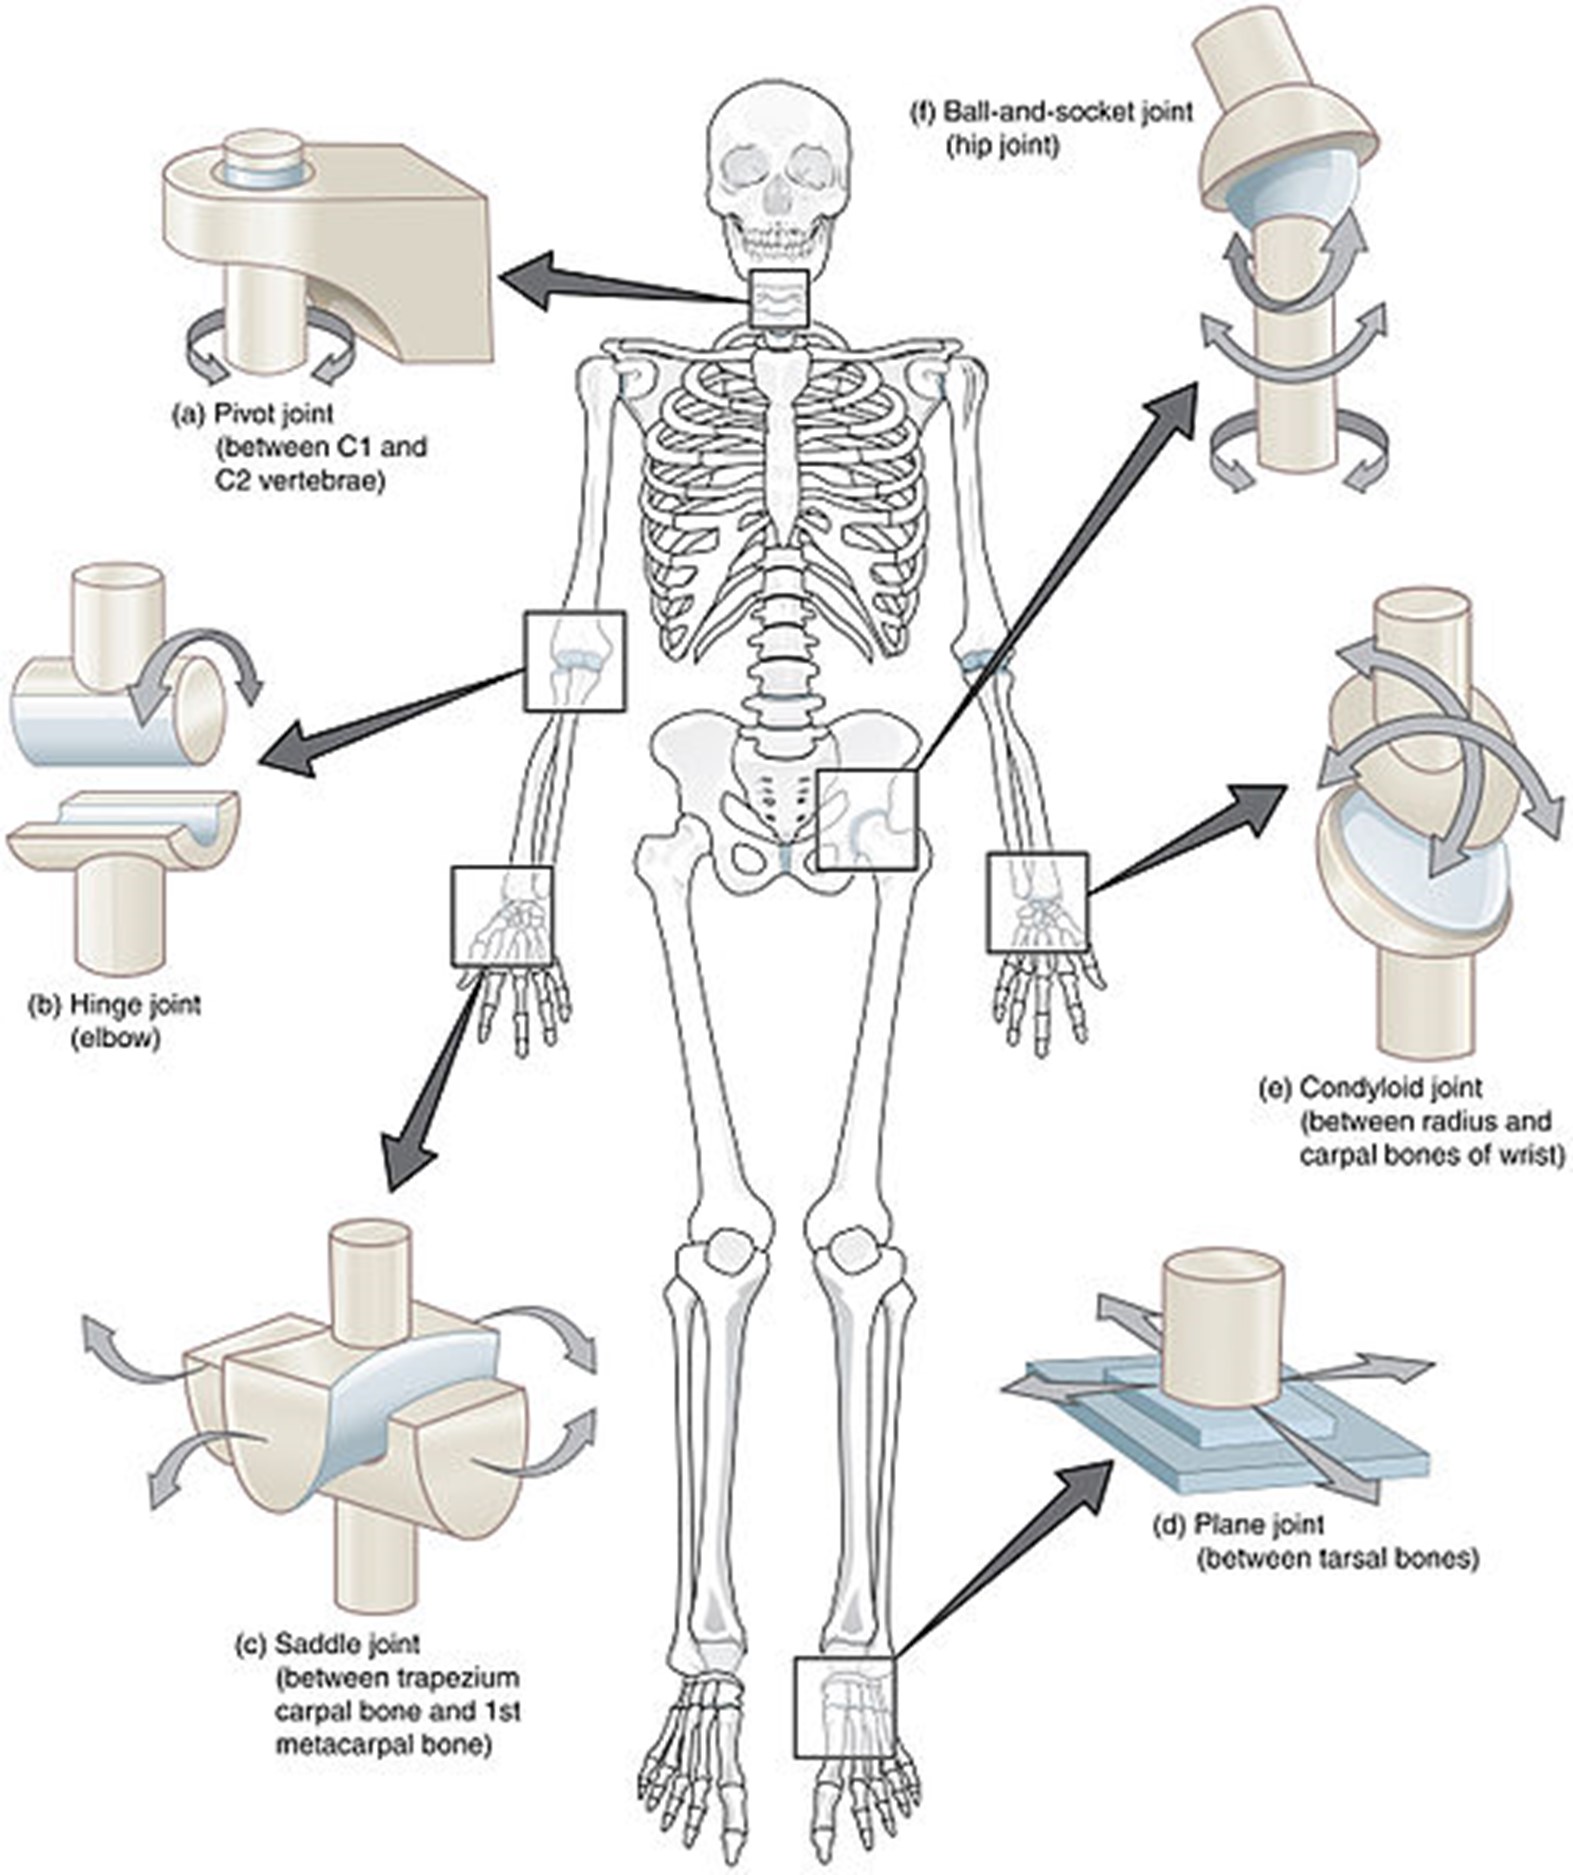

Anatomy and Physiology

The human body contains bones, cartilage, and joints; these facilitate movement. Joints that do not move are called synarthrosis; those with limited movements, such as the symphysis joint, are referred to as amphiarthrosis. Diarthrosis joints freely move and may be categorized as a ball-and-socket, pivot, hinge, saddle, plane, or condyloid joint (see Figure 1). These are synovial joints and contain articular cartilage on the surface of the bones (see Figure 2). Articular cartilage contains connective tissue with an extracellular matrix comprised of water, proteoglycans, ground substance, and collagen. Amino acids and disaccharides are found in the proteoglycans allowing for elasticity, stiffness, and movement. The joint capsule is a fibrous connective tissue that covers and stabilizes the joint. The synovial membrane surrounds the joint capsule and is responsible for secreting synovial fluid, which serves as a buffer in preventing friction or rubbing of the bones, protecting them during movement. Synovial fluid is also housed in bursas, which allow the tendons to move freely. Synovial fluid and articular cartilage collaborate in reducing friction in the joint throughout mobility. Inflammation or wearing down of any part of the joint can contribute to the discomfort associated with arthritis (Scanlon & Sanders, 2019).

Figure 1

Different Kinds of Joints

(Open Stax College, 2013b)